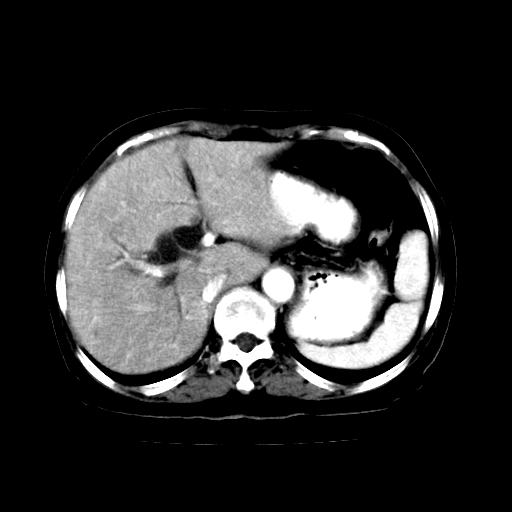

女,74岁,上腹部不适、腹胀两月余,黄染四天。请大家看看肿块周围血管情况。

支持胰头癌伴胆总管及肝内胆管扩张.

胰头癌伴肝内外胆管扩张,胆囊积液.

肝内外胆管及胆囊扩张,胰管扩张,但“双管征”不明显,胆总管下段内见软组织有强化影,肠系膜上静脉推移不是很明显,考虑胆总管下段癌可能大。

胆囊胆总管扩张,胰头与十二指肠间似有一软组织密度灶,胰头增强不均,1壶腹癌,2胰头癌